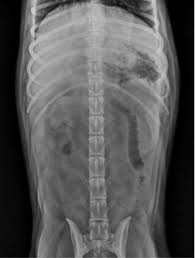

Ultrasonography Of The Abdominal Vasculature Today S Veterinary Practice from todaysveterinarypractice.com Browse our extensive yoga pose library, with a vast collection of basic poses, advanced poses, seated and standing poses, twists, and bandha techniques. A muscular partition separating the. As the pace of veterinary advancement accelerates, even the most experienced veterinary teams are challenged to keep up with all the changes that impact their practice. Miller's anatomy of the dog, ed 4, philadelphia, 2013, wb saunders.) This veterinary anatomical atlas includes 27 scientific illustrations with a selection of labelled structures to understand and discover animal anatomy (skeleton, bones, muscles, joints and viscera). The corpus spongiosum is a vascular tissue sleeve surrounding the urethra. Anatomy synonyms, anatomy pronunciation, anatomy translation, english dictionary definition of anatomy. This veterinary anatomical atlas includes selected labeling structures to help student to understand and discover animal anatomy (skeleton, bones, muscles, joints, viscera, respiratory system.